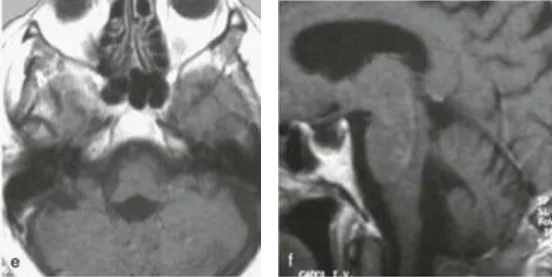

病例一:74岁女性患者

因持续性剧烈头痛与进行性步态不稳就诊,日常行走需搀扶。术前MRI(a-c)显示巨大肿瘤完全占据第四脑室,向下延伸至颅颈交界区,压迫脑干,手术风险高。肿瘤病理为良性室管膜瘤,经INC巴教授手术实现全切(术后MRI见e、f),未新增神经功能障碍。